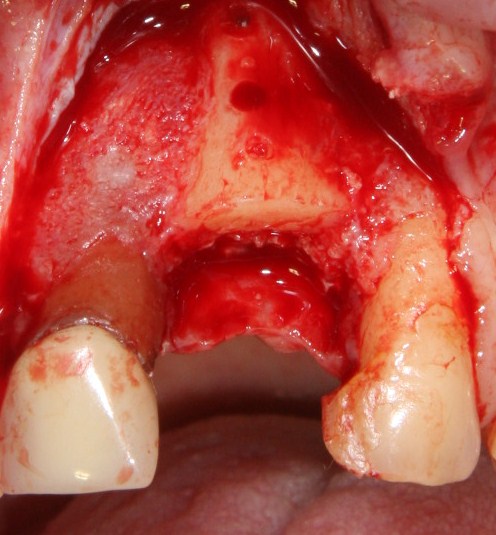

Для удаления зубов мы используем прямой элеватор и тонкие «корневые» щипцы-байонеты. Сама процедура удаления занимает около 10 минут:

Давайте внимательно посмотрим на состояние лунок центральных резцов после удаления:

Приемлемый фенотип (сочетание толщины и ширины участка жевательной десны) — это, конечно, приятно. Но гораздо важнее сосредоточиться на рисках, их на этот момент два:

— травматическое повреждение слизистой, вызванное удаление зубов связано с тем, что при хроническом воспалении слизистая оболочка теряет эластичность, поэтому легко рвётся. Такая ситуация создаёт серьёзную угрозу эстетическому результату лечения, в зависимости от того, насколько быстро десна придёт в норму.

— как и предполагалось после КЛКТ, утрата костной стенки привела к тому, что десна провалилась в просвет лунки левого центрального резца. Это еще больше усугубляет клиническую ситуацию.